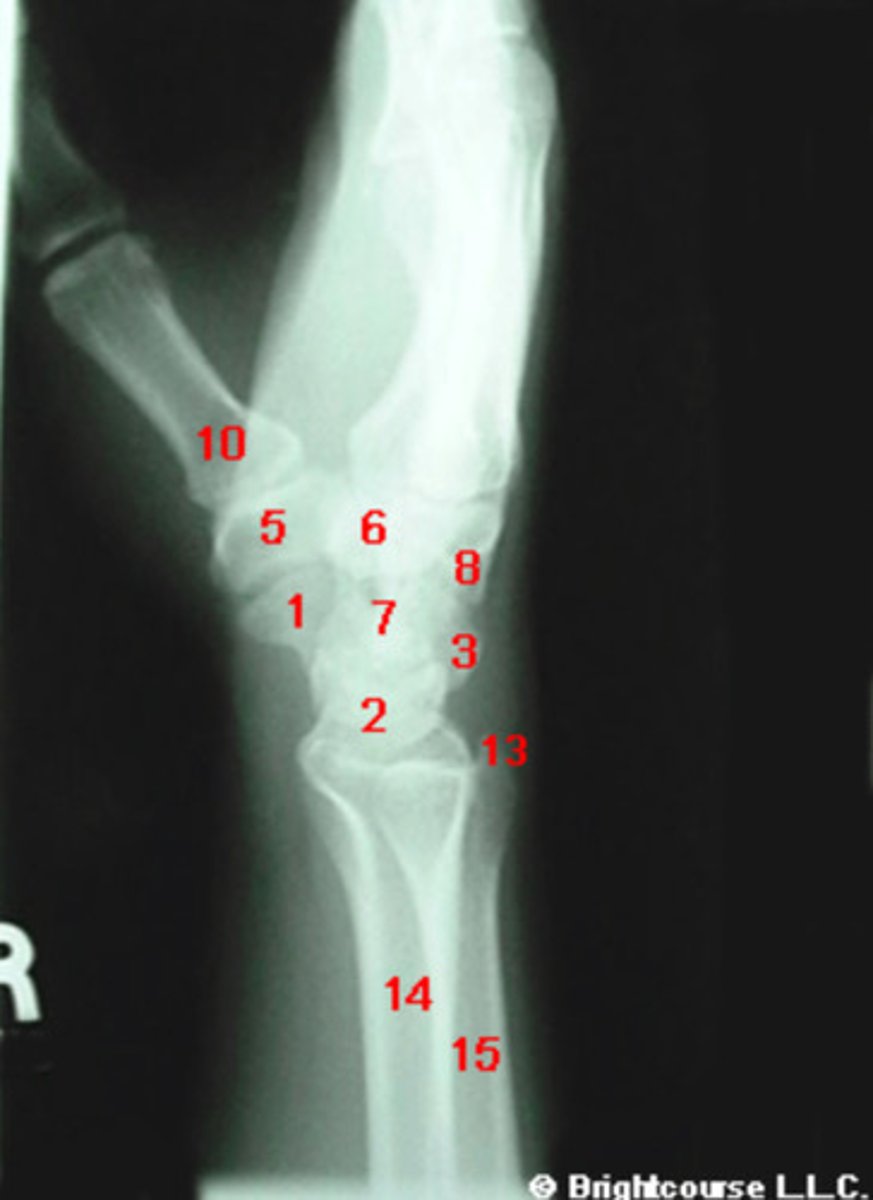

PA, internal oblique, and lateral

What are the standard plain film radiographic projections for the wrist?

Capitate

What structure is indicated by number 7?

Scaphoid

What structure is indicated by number 1?

Lunate

What structure is indicated by number 2?

Triquetrum

What structure is indicated by number 3?

Pisiform

What structure is indicated by number 4?

Trapezium

What structure is indicated by number 5?

Trapezoid

What structure is indicated by number 6?

Hamate

What structure is indicated by number 8?

Styloid process of ulna

What structure is indicated by number 13?

Styloid process of radius

What structure is indicated by number 12?

Base of the first metatarsal

What structure is indicated by number 10?